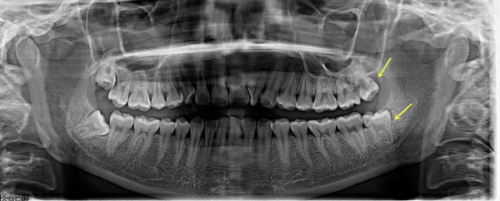

1. 术前评估:种牙前需要进行全方面的口腔检查,包括全景片或 CBCT 检查,评估骨量、咬合空间及牙龈状况。同时,要告知医生自己的全身健康状况,如是否患有糖尿病、高血压、心脏病等疾病,因为这些疾病可能会影响种牙的成功几率。

1. 连缺多颗牙:如果是连缺 6 颗牙这种情况,种植牙比镶烤瓷牙要好些。做种植牙只需植入 3 - 4 颗种植体加上连桥冠,就可以完成修复,而且咀嚼力度、咬合力量都比较好。而镶烤瓷牙需要选择至少两个健康的基牙搭桥,当缺失牙齿数量较多时,可能会面临基牙不够或者基牙不健康的问题,修复成效不理想。